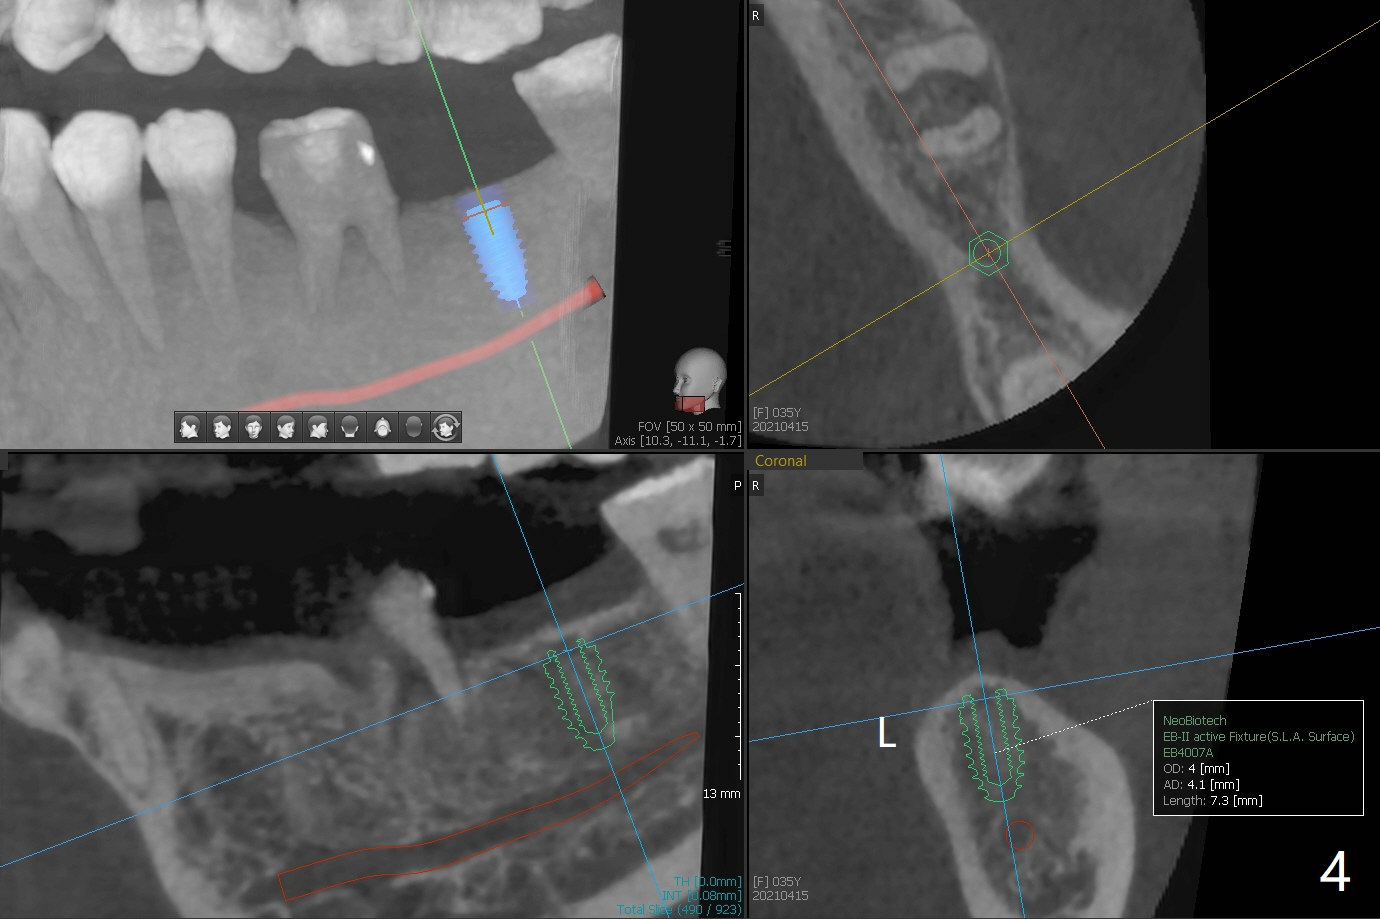

A 35-year-old woman has had guide

Return to No Caries Placement